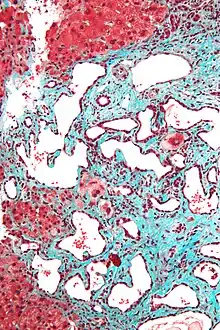

Micrograph of a bile duct hamartoma. Trichrome stain, high magnification

Low magnification micrograph of a bile duct hamartoma. Trichrome stain.